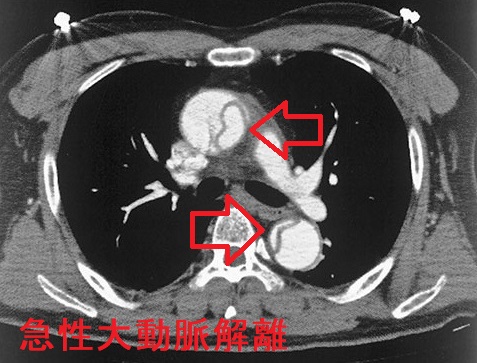

急性大動脈解離(acute aortic dissection: AAD)とは、大動脈壁の脆弱さ、動脈硬化、高血圧などが原因で生じます。血管内膜に亀裂が入り、中膜が裂け、内腔側が内膜フラップ(intimal flap)になって、その下に偽腔が生じる病態です。

急性大動脈解離(AAD)では、大動脈から分枝する動脈が巻き込まれて様々な症状を伴います。

- 手の血圧差、手の冷感、血圧が計測不能(ショック・バイタル)、皮膚の末梢循環障害による網状皮斑

- 腸骨動脈・大腿動脈に解離が及ぶと、下腿が虚血状態になって、大腿動脈触知不能に。下肢血圧差、冷感。皮膚の末梢循環障害による網状皮斑

- 心タンポナーデ(死因の一位)、心筋梗塞、大動脈弁閉鎖不全症(AR)(下記)

Stanford B型急性大動脈解離(DeBakey III)で主要分枝を含まない領域に限局している場合は降圧治療のみ(降圧目標は収縮期血圧105~120mmHg、β遮断薬が第一選択)。